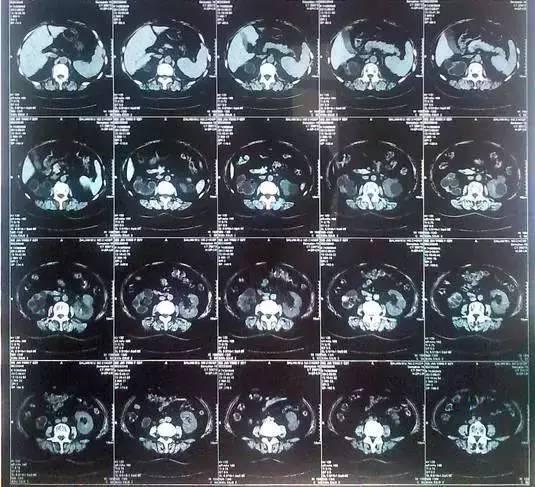

55歲的老何是金華東陽市橫店鎮(zhèn)人,一名普通工人。因?yàn)轭l繁腰疼去醫(yī)院檢查,結(jié)果CT顯示,他的左腎里竟然密密麻麻布滿了石頭,幾乎把整個(gè)腎都塞滿了,手術(shù)從左腎取出了420顆結(jié)石!

醫(yī)生看了CT的結(jié)果顯示,非常嚴(yán)肅的告訴他,他的左腎已經(jīng)被結(jié)石占滿,必須馬上手術(shù)治療。這次手術(shù)讓主刀醫(yī)生觸目驚心,他們居然從老何的左腎取出了420顆結(jié)石。這是他們手術(shù)生涯上從來沒有遇到過的病例。